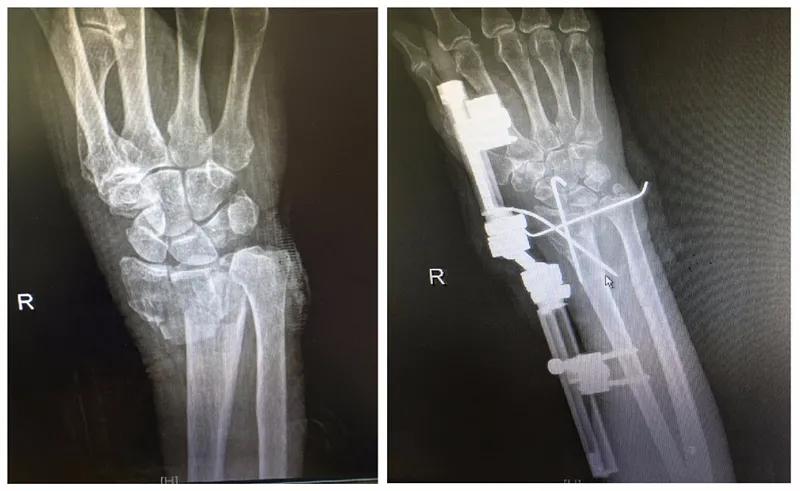

经急诊行“右左膝+右腕部+骨盆X线”提示,陈奶奶的 右桡骨远端粉碎性骨折 , 右尺骨茎突撕脱性骨折 ,右腕部软组织肿胀。经家属同意,在厦门莲花医院莲河总院骨科主任医师冯健翀的主刀下,陈奶奶在全身麻醉的状态下,行臂丛麻醉下行 右腕部清创+尺骨复位+桡骨闭合复位克氏针内固定+外支架固定术 ,手术顺利,麻醉效果好,术后安返病房。

“陈奶奶属于高龄患者,心肺功能较差,手术麻醉耐受能力差,特别要注意的是,术中及术后出现心脑血管病变手术风险较大。 手术主要是给予陈奶奶骨折复位及外固定支架固定,因为其既往有老年痴呆病史,因此更应该要加强术后护理。 ”冯健翀主任医师表示。